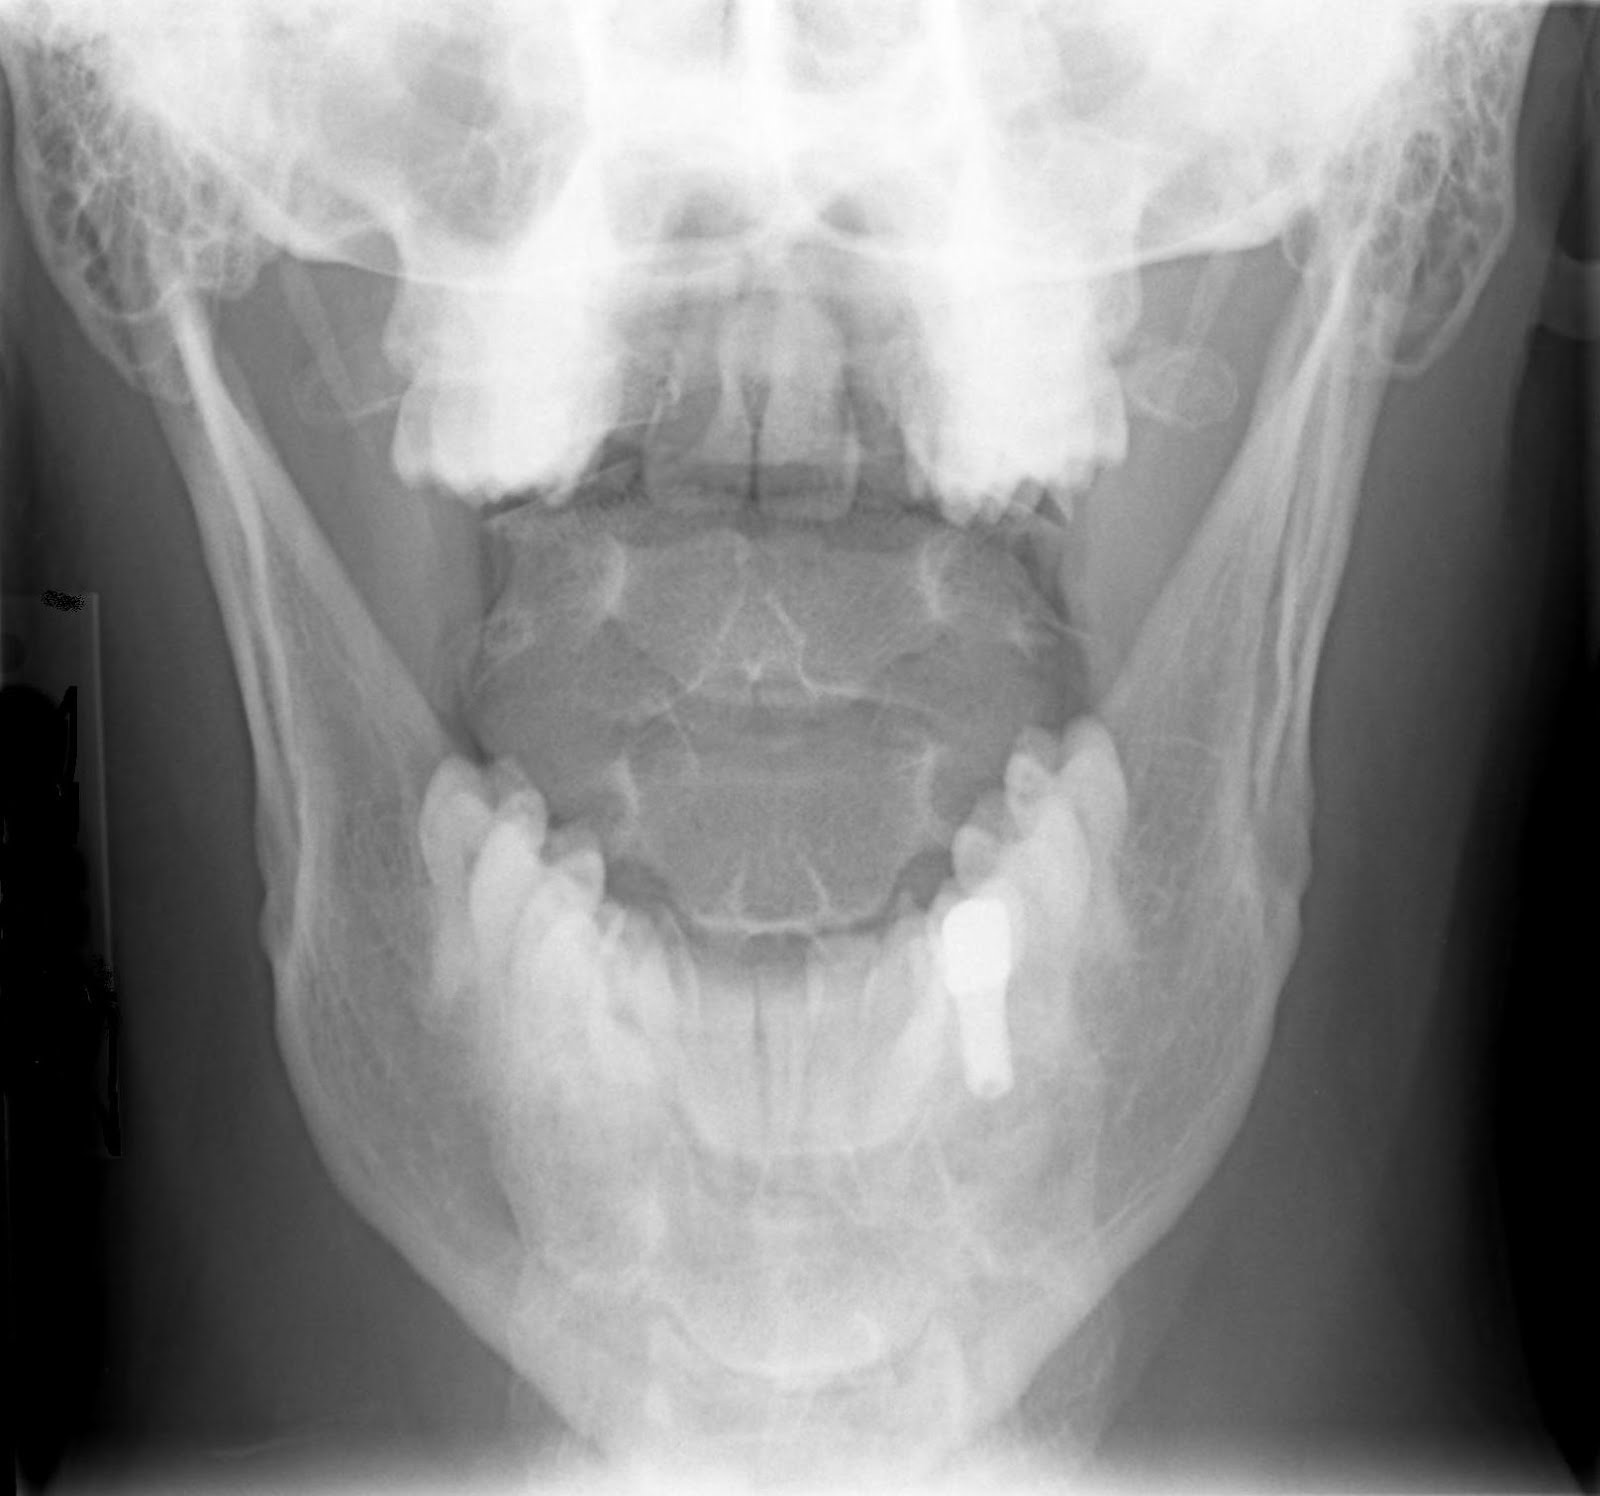

Lateral radiograph (A) and open mouth view (B) showing a posterolateral Dens Fracture X Ray As expected, most fatal cervical spine injuries occur at. Odontoid fracture (lateral) and odontoid fracture. Most dens fractures are caused by motor vehicle accidents and falls. This review article attempts to provide the basic framework required for accurate interpretation of cervical spine imaging with a. Odontoid fractures are relatively common fractures of the c2 (axis) dens that can be seen. Dens Fracture X Ray.

Odontoid lateral mass asymmetry do we overinvestigate? Emergency Dens Fracture X Ray Odontoid fracture (lateral) and odontoid fracture. Odontoid process fracture, also known as a peg or dens fracture, occurs where there is a fracture through the odontoid process. Mri is a valuable imaging modality for the diagnosis and evaluation of odontoid (dens) fractures due to its detailed visualization of bone marrow and assessment of supporting. The odontoid process fracture (also known. Dens Fracture X Ray.